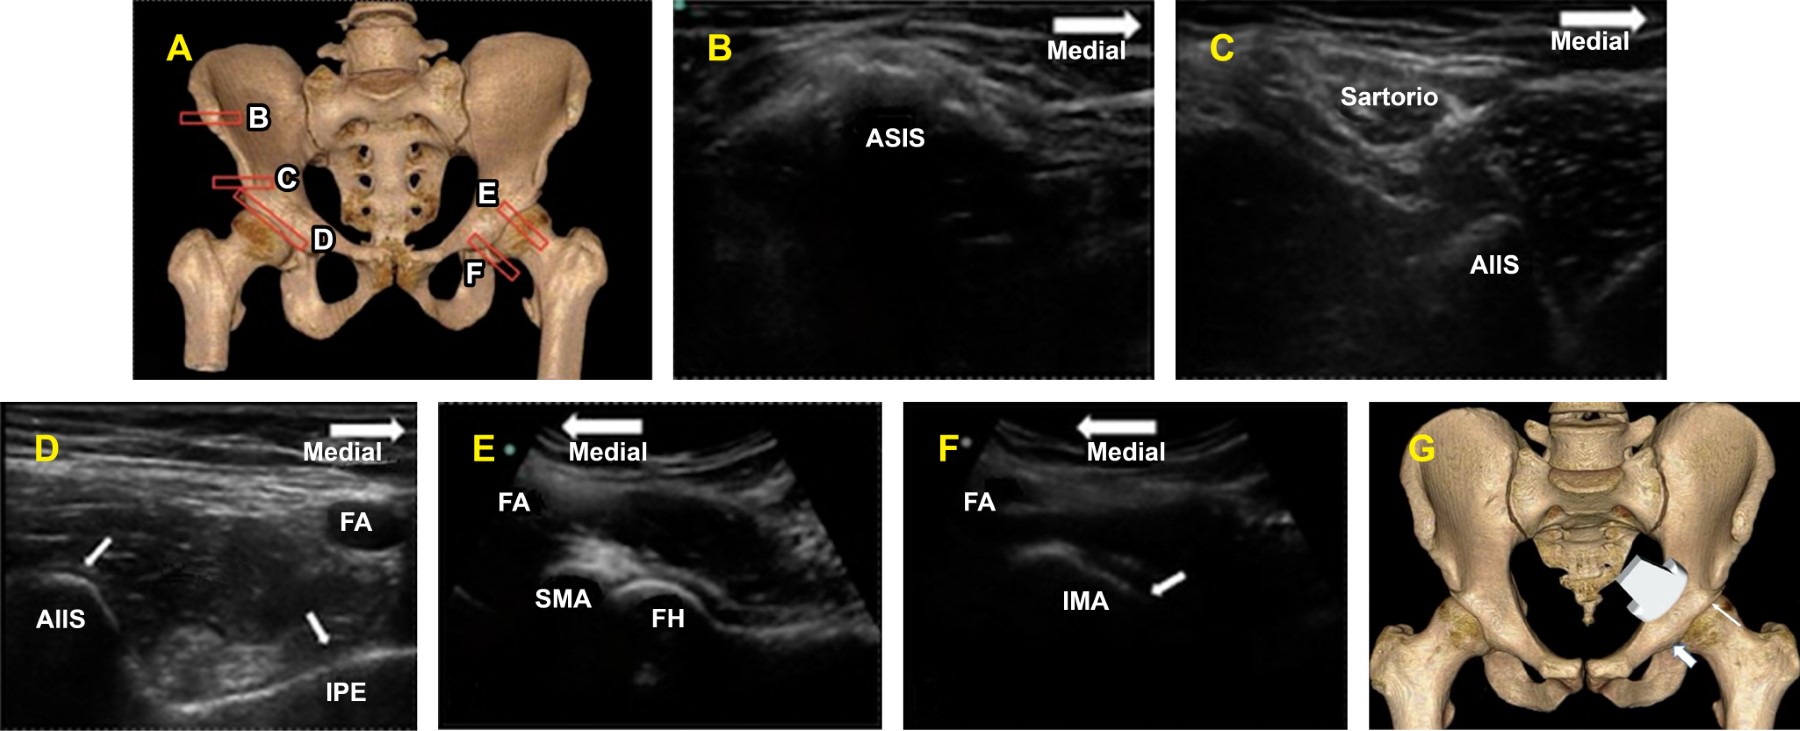

En este contexto, las técnicas anestésicas multimodales de mínima invasión con esquemas optimizados para la disminución del consumo de opioides y sus efectos adversos cobran relevancia.5 Una técnica emergente propuesta es el bloqueo del grupo de nervios pericapsulares de la cadera (Pericapsular Nerve Group, PENG por sus siglas en inglés), descrito a finales de 2018 por los Doctores Girón-Arango y Peng6 basados en el estudio anatómico del Dr. Short, en el que se demostró que los nervios femoral, obturador y obturador accesorio juegan un papel predominante en la inervación de la articulación de la cadera (Figura 1), y que identificó las referencias anatómicas que facilitan el abordaje ecoguiado (Figura 2).7

Técnica anestésica: en sala quirúrgica bajo monitoreo estándar II de la ASA, con oxígeno suplementario por puntas nasales a 2 L/min en decúbito supino, se realizó asepsia de la región ilioinguinal ipsilateral a la fractura con clorhexidina 2%, se utilizó un transductor lineal de alta frecuencia con protección estéril y gel de interfaz colocándose en plano transverso sobre la espina iliaca anteroinferior, se realizó rotación medial a 45o aproximadamente hasta localizar la eminencia iliopúbica. Las estructuras a identificar son la arteria y vena femorales, los nervios femoral, obturador y obturador accesorio y el tendón del músculo psoas (Figura 3). Se utilizó una aguja Stimuplex de 22 G de 100 mm ecogénica. Con técnica in plane, se depositaron 30 mL de ropivacaína 0.5%, verificando su difusión en el plano musculofascial entre el tendón y la rama púbica. Quince minutos después, se colocó al paciente en decúbito lateral sobre el lado contrario a la fractura, se procedió al bloqueo neuroaxial con técnica subaracnoidea dosis única con aguja Whitacre 27 G ministrando 10 mg de bupivacaína isobárica. Durante el transanestésico, sólo se agregó paracetamol de 1 g y parecoxib de 40 mg como medicación analgésica y se continuó con horario. En caso de requerir analgesia adicional durante el periodo de evaluación, se utilizó tramadol 50 mg como rescate.

Figura 2